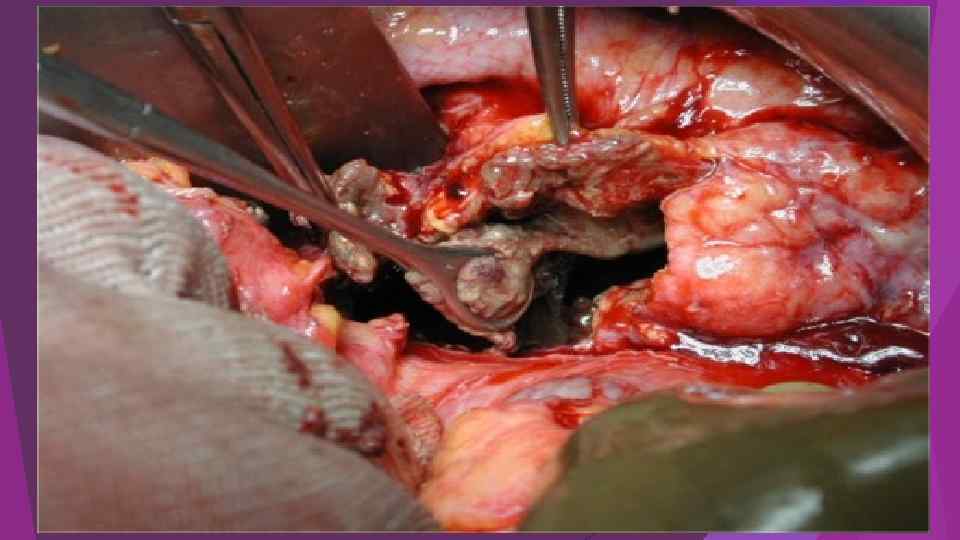

Инфицированный панкреонекроз инфицированный панкреонекроз представлен серо-черной неоднородной массой замазкообразной консистенции, не имеющий капсулы - стенки или сформировавшейся капсулы с мутным, типа «мясных помоев» или гнойным эксудатом с микроабсцессами в паренхиме и забрюшинной клетчатке. Балалыкин А. С. , Луцевич О. Э. , Галлямов Э. А. , 2007

Инфицированный панкреонекроз инфицированный панкреонекроз представлен серо-черной неоднородной массой замазкообразной консистенции, не имеющий капсулы - стенки или сформировавшейся капсулы с мутным, типа «мясных помоев» или гнойным эксудатом с микроабсцессами в паренхиме и забрюшинной клетчатке. Балалыкин А. С. , Луцевич О. Э. , Галлямов Э. А. , 2007